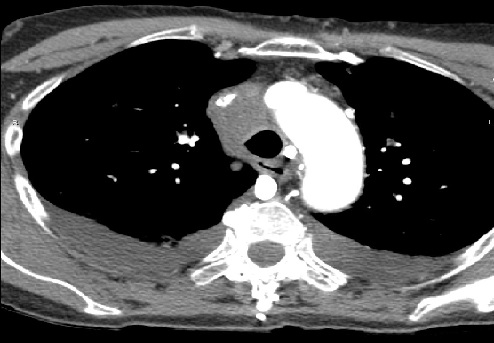

El hemangioendotelioma epitelioide pulmonar es una enfermedad oncológica infrecuente de origen endotelial, con una incidencia inferior a un caso por millón de habitantes. Habitualmente se comporta como un neoplasia de bajo grado; sin embargo, se han descrito algunos casos en los que el tumor manifiesta una alta agresividad, extendiéndose con rapidez por todo el organismo. Presentamos el caso de una mujer de 77 años que fue diagnosticada de un hemangioendotelioma epitelioide pulmonar metastásico con sintomatología severa, precisando tratamiento urgente para su paliación.